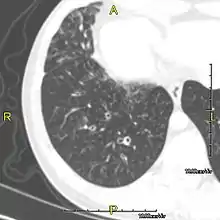

Sagittal CT image showing "tree in bud" appearance of mucous impaction in distal small airways related to primary ciliary dyskinesia

CT image showing dilated and thickened medium-sized airways (bronchiectasis) in a patient with Kartagener syndrome

Oblique sagittal CT image showing lower lobe cylindrical bronchiectasis in the same patient